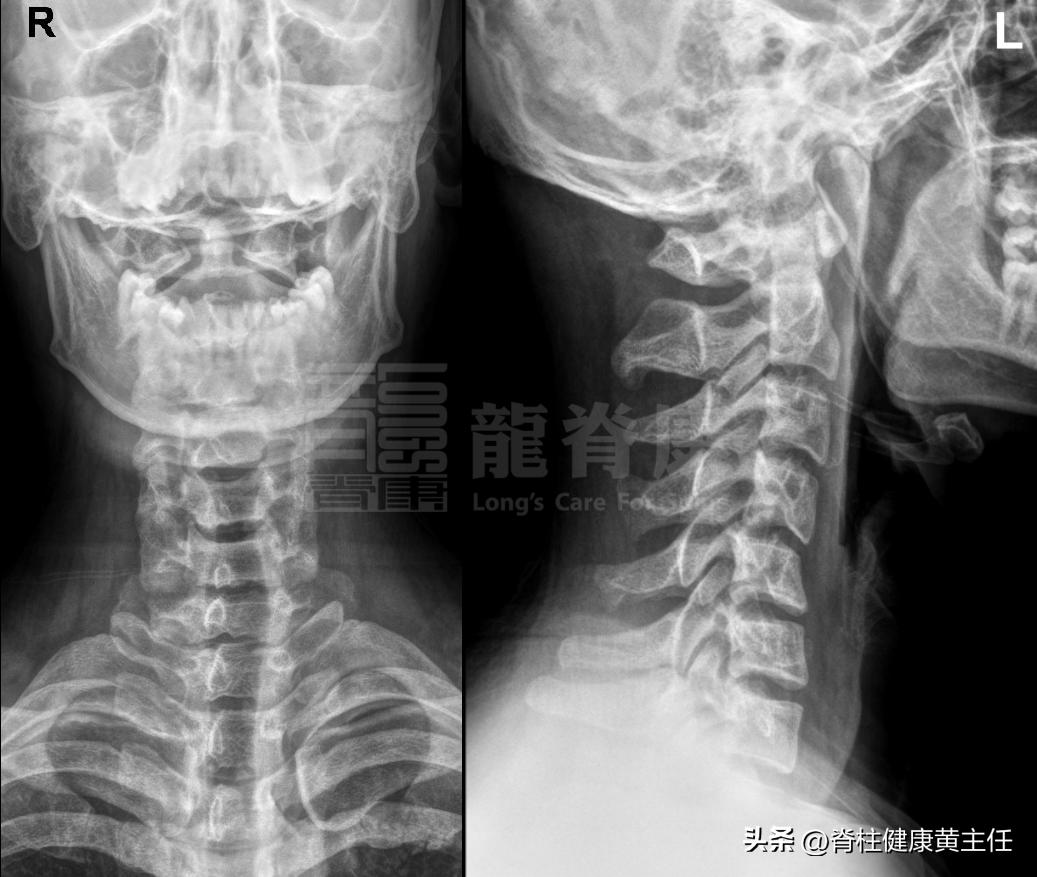

2、影像检查:X光片可见C4前滑脱错位,C4左后旋。

医生总结结合患者外伤史、主诉、体格及影像学检查,判断该案例为颈椎挥鞭样损伤。治疗以手法调整错位的颈胸椎及肋骨结构为主,缓解后及时介入个体化康复训练,增强颈椎动态稳定性,以恢复功能、预防复发。